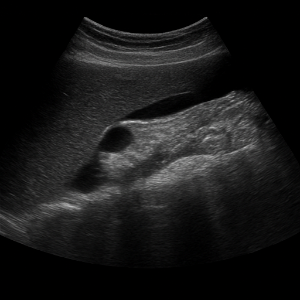

간

간은 복부초음파에서 가장 먼저 살펴보는 장기예요. 초음파로 지방간, 간경변, 결절, 낭종, 혈관종, 간암 등 여러 가지 변화를 감지할 수 있고, 간 기능 검사에 이상이 있을 때 특히 중요하게 확인해요.

간 질환

- 지방간

간에 기름이 쌓이면 초음파에서 밝고 반짝이는 모습으로 보일 수 있어요. 요즘 지방간이 흔한데, 초음파로 쉽게 확인되서 유용합니다. - 간경변

만성 염증으로 간이 딱딱해지고 울퉁불퉁해지는 상태예요. 초음파에서 간 표면이 거칠고 모양이 변형된 모습으로 나타나요. - 간암(간 종양)

덩어리나 혹처럼 생긴 이상이 초음파 화면에 포착될 수 있어요. 양성 종양인지 악성인지 구분하려면 추가 검사가 필요할 때도 있어요.